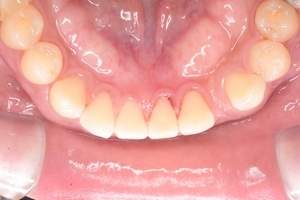

歯石除去

治療前

治療後

| 年齢 | 25歳・男性 |

| 主訴 | 歯石をとりたい・検診 |

| 治療内容 | 各種検査・歯石除去 |

| 治療期間 | 60分 |

| 費用 | 初診料3,000〜4,000円前後 +歯石除去約1,000円 |

| リスク・副作用 | ・処置後に歯がしみることがあります。 ・歯と歯の間に隙間ができるので、息が漏れ発音しにくいと感じることがあります。 ・歯ぐきの炎症が軽減すると歯ぐきが引き締まり、歯が長く見えることがあります。 |

| 担当者所見 | 前歯の裏側にすぐに歯石が溜まってしまいザラザラして気になるとご相談いただいたので適切な歯ブラシの当て方とフロスの通し方をお伝えさせて頂きました。 |